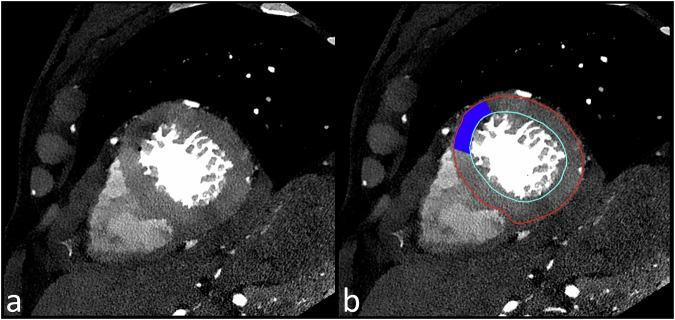

Background: Spectral photon-counting computed tomography (SPCCT) outperformed dual-energy computed tomography (DECT) for coronary artery stenosis assessment. However, data about myocardial perfusion imaging (MPI) is lacking. This feasibility study aimed to evaluate and compare the diagnostic performance of SPCCT and DECT for rest MPI in patients with hemodynamically significant coronary stenoses, using invasive coronary angiography (ICA) and invasive fractional flow reserve (FFR) as reference standards.

Materials and methods: Eighteen very-high-risk patients with hemodynamically significant coronary stenoses at ICA underwent both dual-layer DECT and SPCCT coronary CT within three days. The sensitivity, specificity, and accuracy of MPI in detecting myocardial hypoperfusion were assessed. Quantitative attenuation differences between normal and hypoperfused myocardial segments were compared for both modalities. Interobserver variability was assessed with a weighted kappa analysis.

Results: SPCCT demonstrated comparable overall performance to DECT for MPI, with an overall sensitivity, specificity, and accuracy of 73.3%, 79.2%, and 76.9%, respectively, versus 73.3%, 75%, and 74.4% for DECT. SPCCT outperformed DECT in the left anterior descending artery territory, achieving a sensitivity of 87.5%, specificity of 100%, and accuracy of 90%, versus 62.5%, 50%, and 60% for DECT. For each CT system, attenuation analysis revealed differences between normal and hypoperfused segments, with mean differences of 17.9 HU for DECT and 15.8 HU for SPCCT (p < 0.05). Inter-reader agreement was higher for SPCCT (κ = 0.86) compared to DECT (κ = 0.62).

Conclusion: SPCCT and DECT provided similar diagnostic performance for rest MPI in a very-high-risk patient cohort, demonstrating comparable effectiveness in detecting the effects of hemodynamically significant coronary stenosis.

Relevance statement: Hemodynamically significant stenosis in very-high-risk patients results in myocardial hypoperfused areas at rest that can be detected equally well with dual-layer CT and spectral photon counting CT, albeit with better reproducibility for the latter.

Key points: SPCCT and DECT showed comparable performance for MPI at rest in very-high-risk patients. The differences between normal and hypoperfused segments were of 17 HU and 16 HU on conventional images for DECT and SPCCT. SPCCT showed higher interobserver agreement compared to DECT, suggesting improved reproducibility.